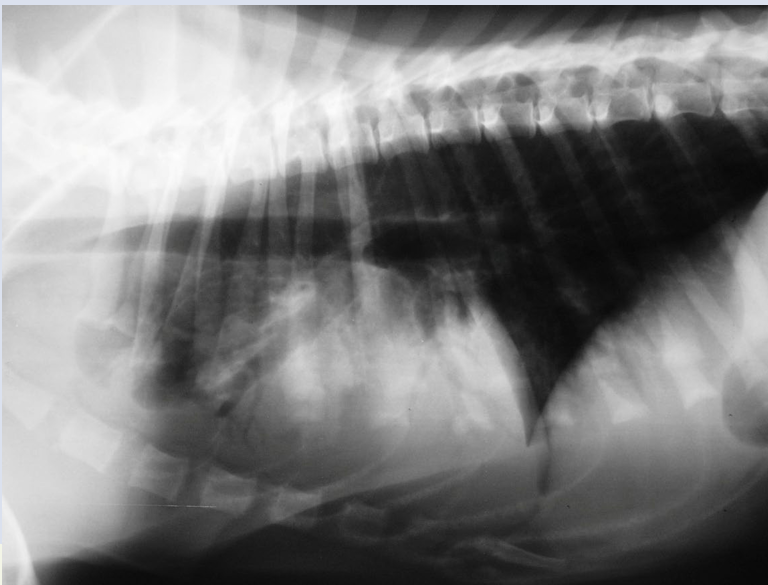

Alveolar pattern on Cranial lobe

have edema/hemorrhage

no margin or ill-defined border

Findings: Hemorrhagic lung